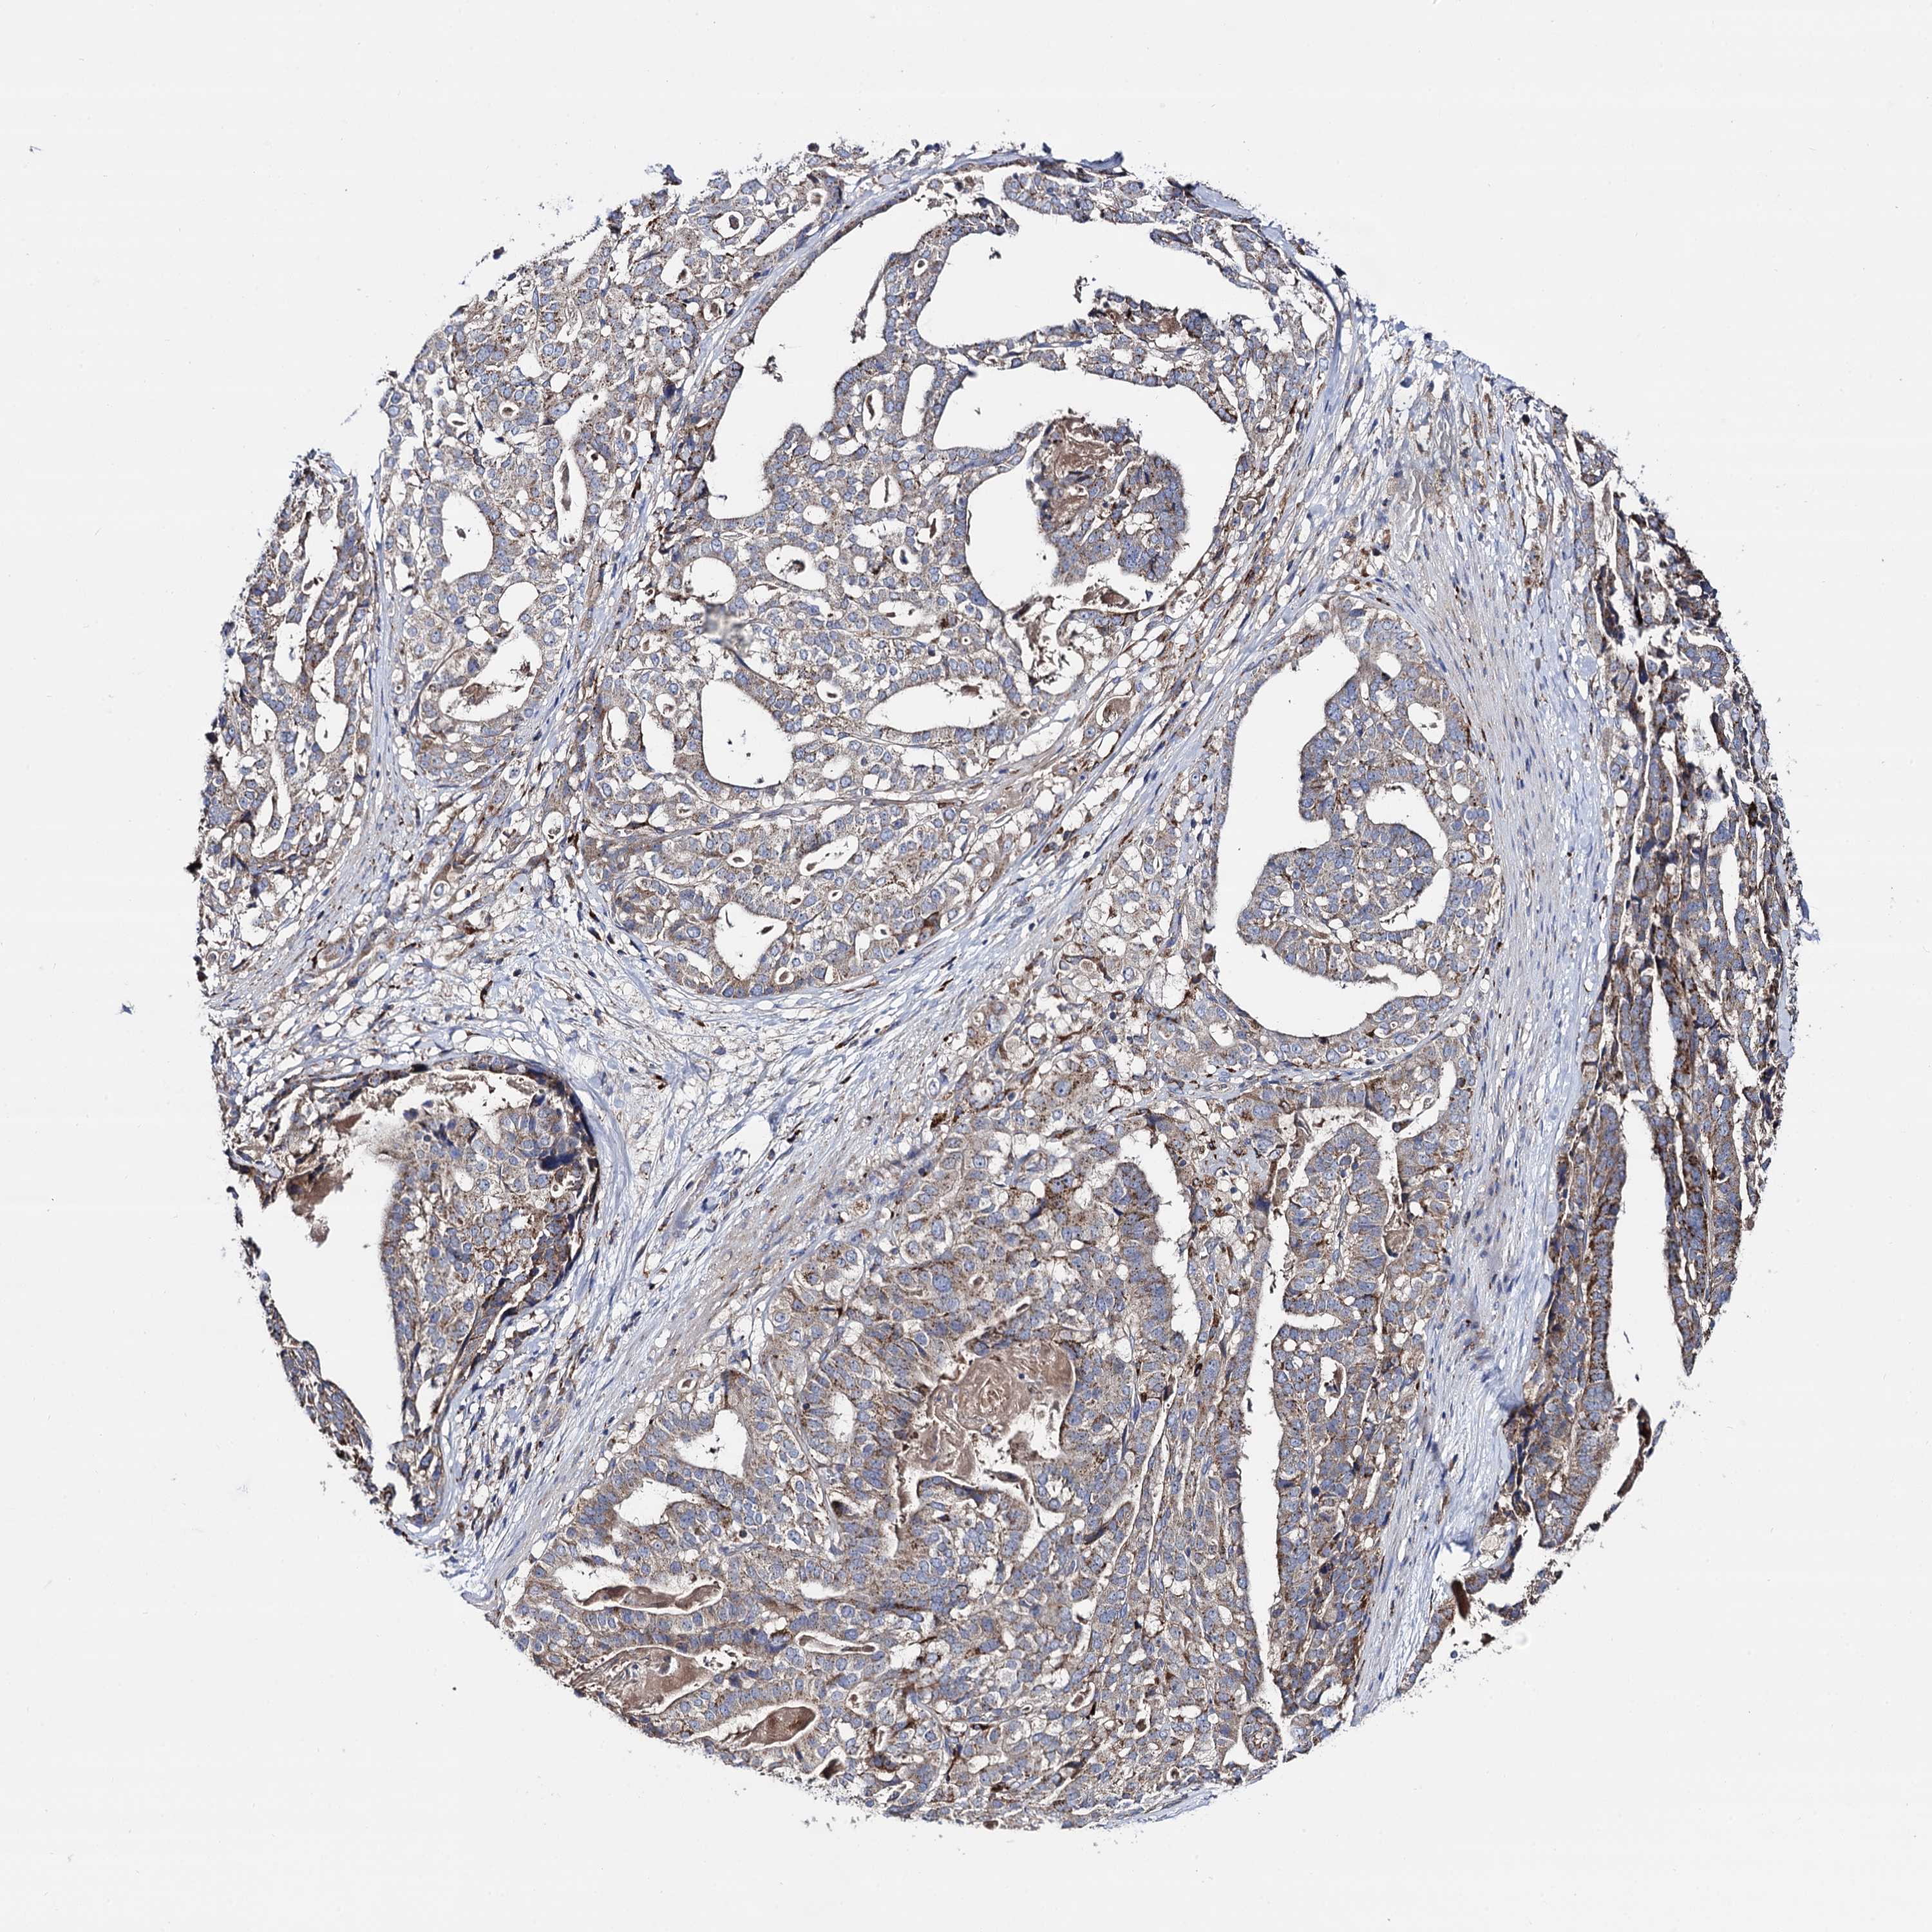

STOMACH CANCER - Protein expressioni

A mouse-over function shows sample information and annotation data. Click on an image to view it in a full screen mode. Samples can be filtered based on level of antibody staining by selecting one or several of the following categories: high, medium, low and not detected. The assay and annotation is described here.

Note that samples used for immunohistochemistry by the Human Protein Atlas do not correspond to samples in the TCGA dataset.

Antibody stainingi

Antibody staining in the annotated cell types in the current human tissue is reported as not detected, low, medium, or high, based on conventional immunohistochemistry profiling in selected tissues. This score is based on the combination of the staining intensity and fraction of stained cells.

Each image is clickable and will lead to virtual microscopy that enables deeper exploration of all samples and also displays staining intensity scores, fraction scores and subcellular localization as well as patient and tissue information for each sample.

Antibody HPA040845

Staining

High

Intensity

Strong

Quantity

>75%

Location

Nuclear

Adenocarcinoma, NOS

Adenocarcinoma, High grade